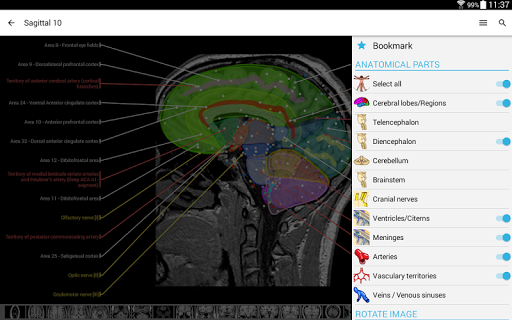

IMAIOS e-Anatomy adalah atlas anatomi manusia untuk dokter, ahli radiologi, mahasiswa kedokteran, dan teknisi radiologi. Dapatkan cuplikan lebih dari 26.000 gambar medis dan anatomi secara gratis sebelum berlangganan atlas anatomi manusia terperinci kami.

e-Anatomy didasarkan pada atlas daring IMAIOS e-Anatomy yang telah memenangkan penghargaan. Bawalah referensi anatomi manusia terlengkap, ke mana pun Anda pergi, di perangkat seluler atau tablet Anda.

e-Anatomy memiliki lebih dari 26.000 gambar yang berisi serangkaian gambar dalam tampilan aksial, koronal, dan sagital serta radiografi, angiografi, gambar diseksi, bagan anatomi, dan ilustrasi. Semua gambar medis diberi label dengan cermat, lebih dari 967.000 label tersedia dalam 12 bahasa termasuk Terminologia Anatomica Latin.

- Pilih label anatomi berdasarkan kategori

Tangkapan layar adalah bagian dari aplikasi e-Anatomy lengkap dengan semua modul diaktifkan. ⚠️ SANGGAHAN PENTING: Ini adalah aplikasi pendidikan independen yang TIDAK berafiliasi dengan atau didukung oleh lembaga pemerintah, bank, atau badan penyelenggara ujian resmi mana pun. Bahasa Indonesia: Untuk informasi resmi dan pembaruan terkait Ujian, silakan kunjungi: Untuk informasi ujian yang autentik, selalu rujuk ke: • SSC: https://ssc.nic.in • IBPS: https://www.ibps.in • RRB: https://www.rrbcdg.gov.in Aplikasi GK dan Current Affair 2025 Hindi menyediakan GK dalam bahasa Hindi, Current Affairs dalam bahasa Hindi, Ujian tiruan dengan Peringkat Seluruh India, Bakat dalam bahasa Hindi, Penalaran dalam bahasa Hindi, Bahasa Inggris, Komputer dalam bahasa Hindi, Perbankan dalam bahasa Hindi, Catatan Soal Tahun Sebelumnya, dll., Soal Pilihan Ganda, Ujian Tiruan untuk Ujian SSC, Ujian Kereta Api, Ujian Perbankan, Kepolisian Negara Bagian, PCS Negara Bagian, Ujian Tingkat Negara Bagian, dll.